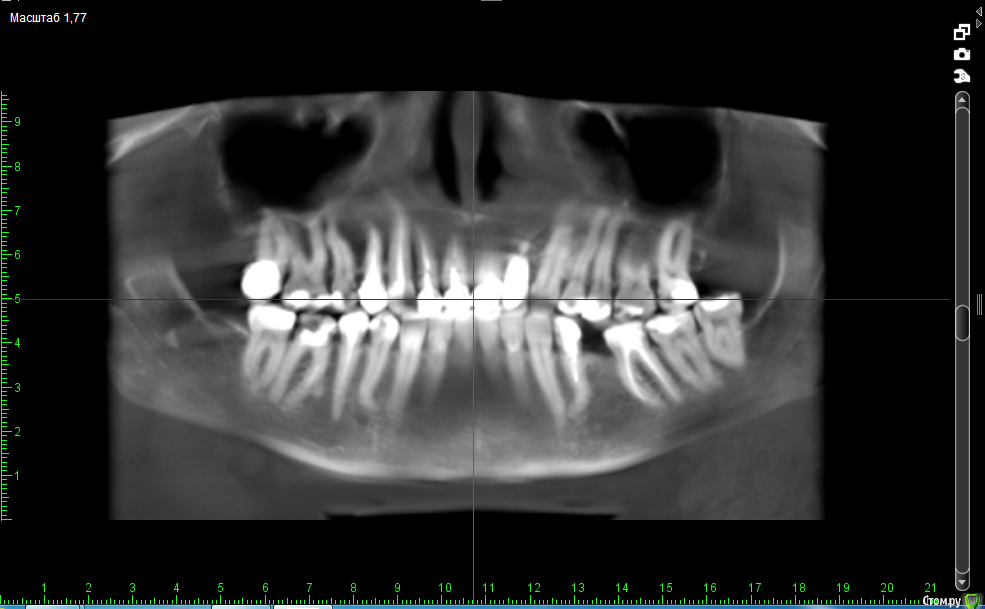

Добрый день, уважаемые доктора. При планировании плана лечения стоматологи рекомендуют удалить несколько зубов:

17 - большая пломба

36 - киста зуба (сделала отдельный скриншот)

34 - невозможность запломбировать канал до конца из-за изогнутого корня

46 - большая пломба и сломан инструмент в канале.

38 - говорят, что вообще не нужен.

Действительно ли надо удалять все эти зубы или можно поставить коронку на 17; перепломбировать 34 или вообще его не трогать, он меня не беспокоит; вылечить кисту на 36 зубе.

post-37334-0-32128200-1512417396_thumb.png